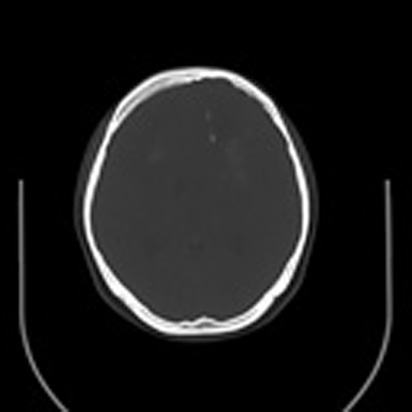

标题: CT16829:女,36,近20天偶有口眼歪斜短暂发作史,近日头痛。 [打印本页]

标题: CT16829:女,36,近20天偶有口眼歪斜短暂发作史,近日头痛。

近20天偶有口眼歪斜短暂发作史,近日头痛。患者先做ct发现病变后又做了mri检查,前日上传2次ct图像均未成功,今日补上。

大脑中线部位肿瘤向两侧生长,可见明显钙化影,考虑少枝胶质瘤,建议增强除外脑膜瘤

左额混杂密度肿块,经胼胝体跨越中线向右额叶生长,多考虑少支胶质细胞瘤,建议mr增强扫描,待排除血管畸形。